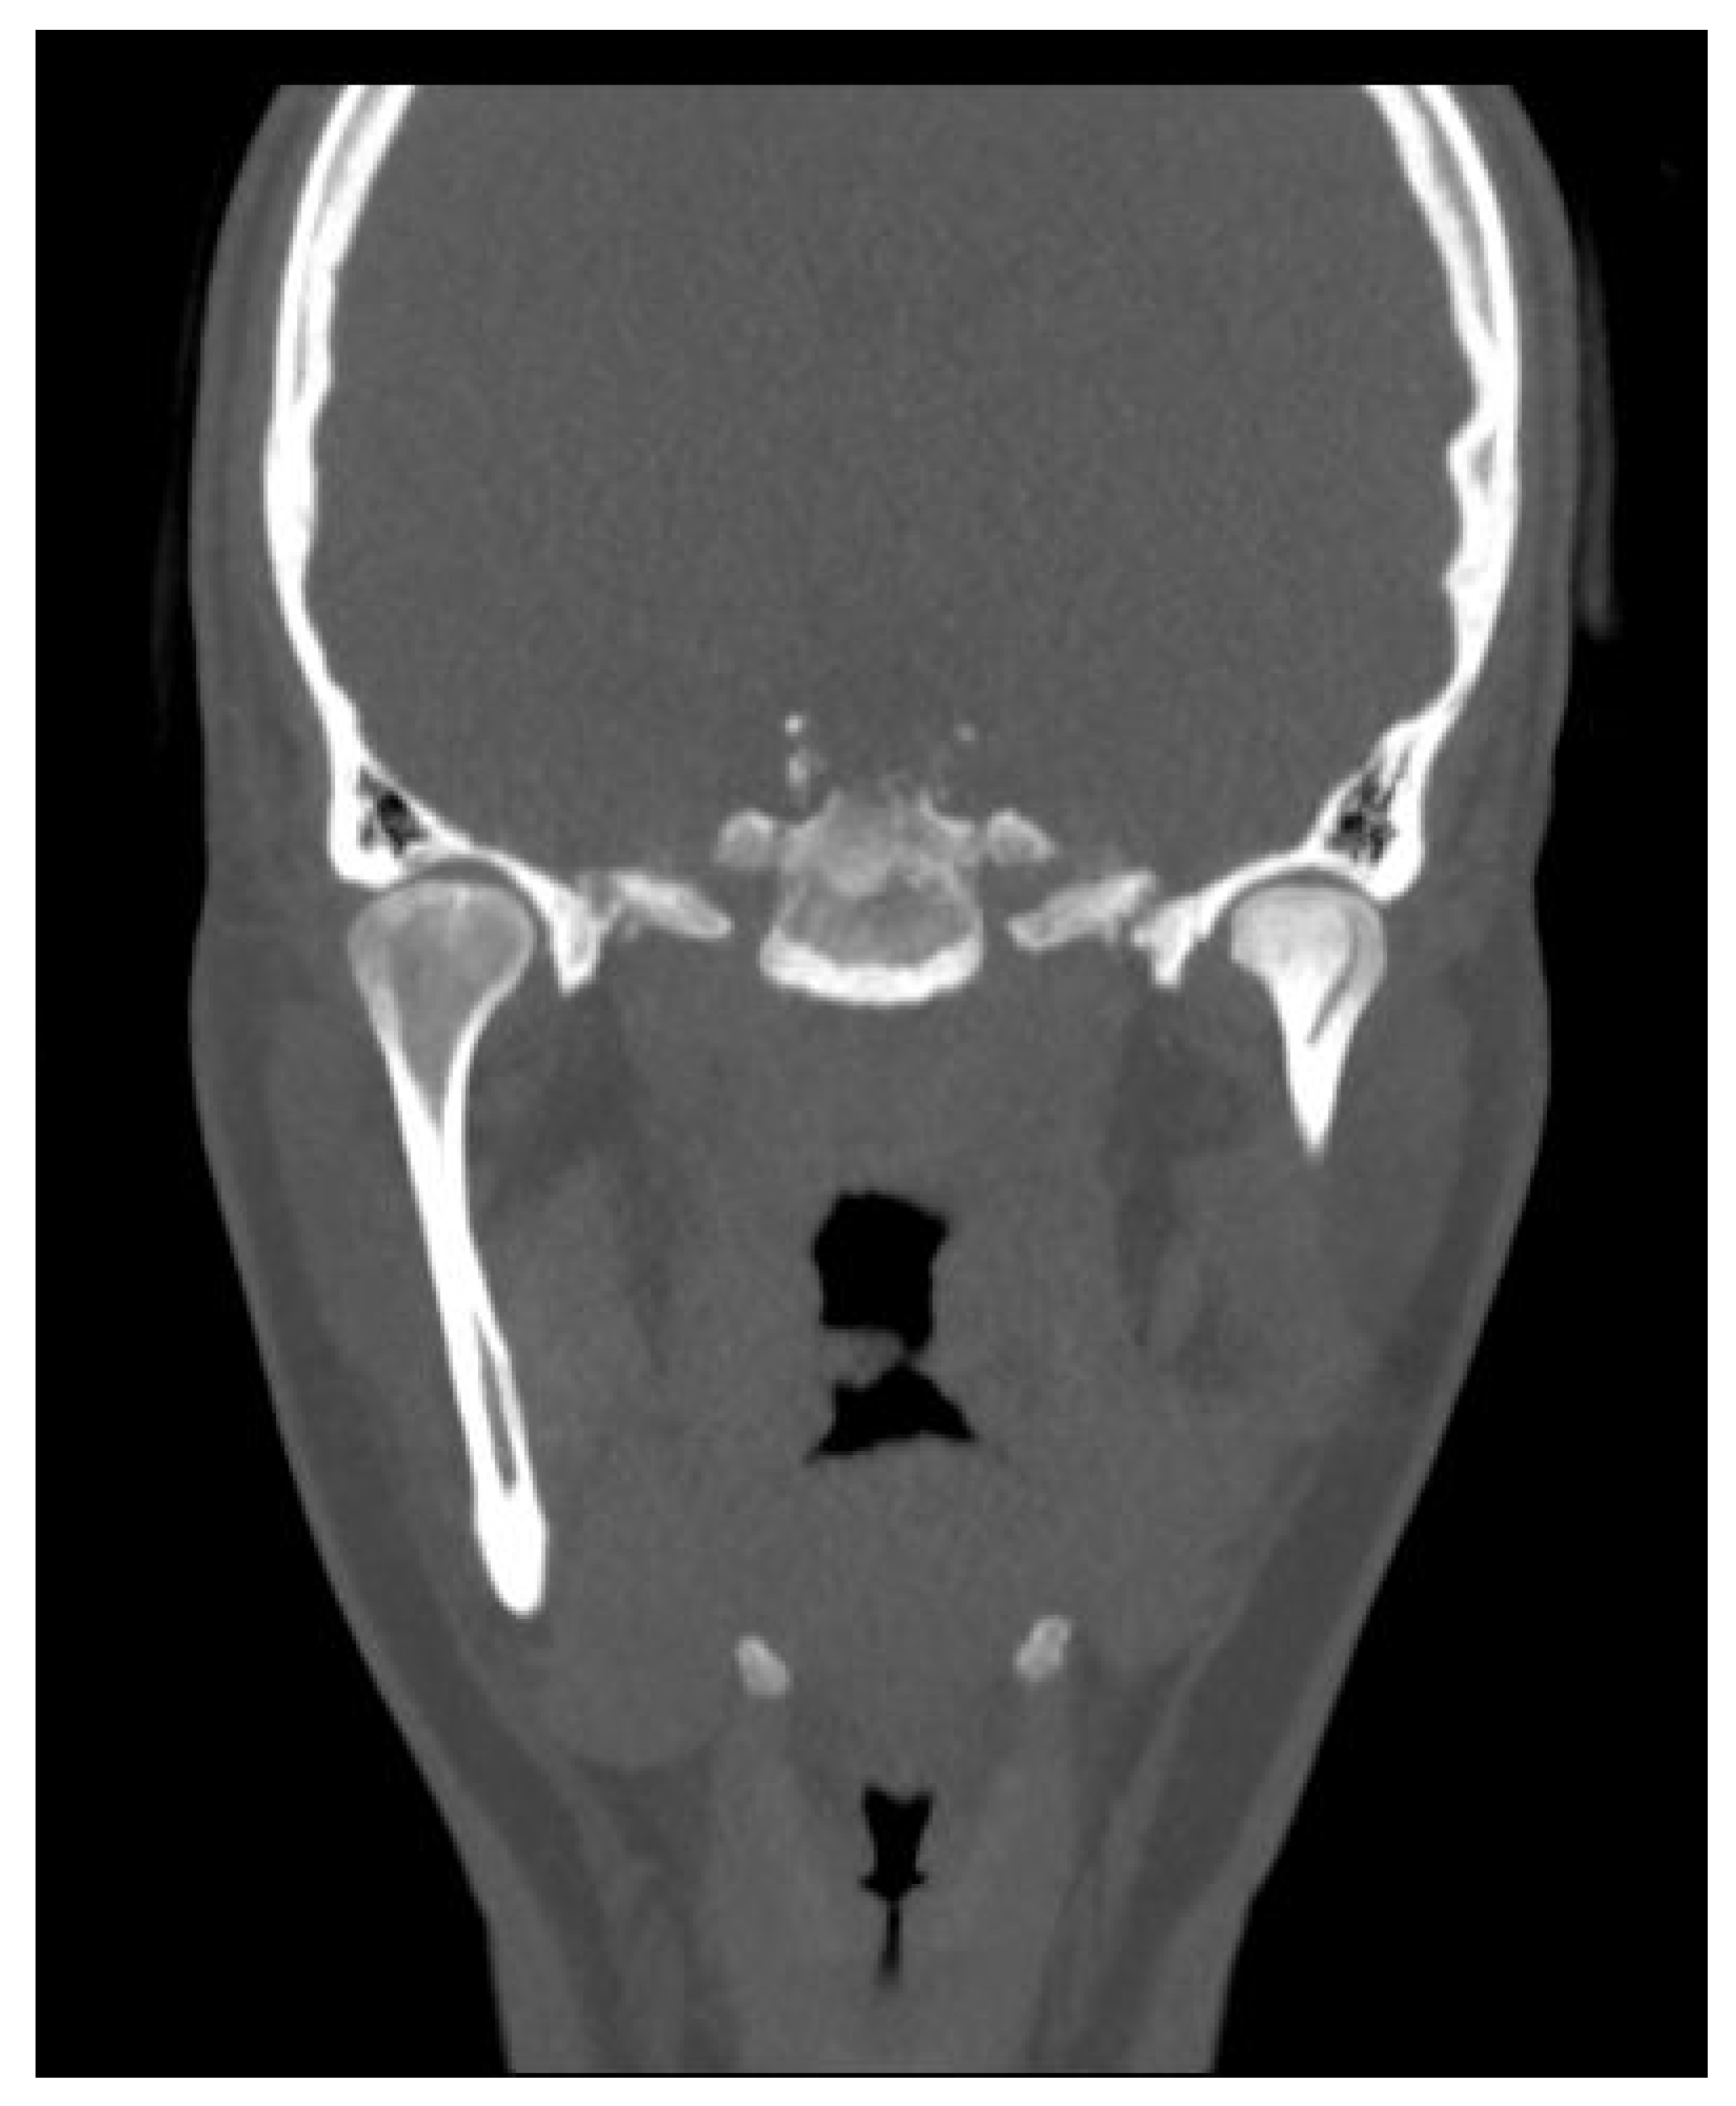

5.1. Panoramic Radiographs and Computed Tomography